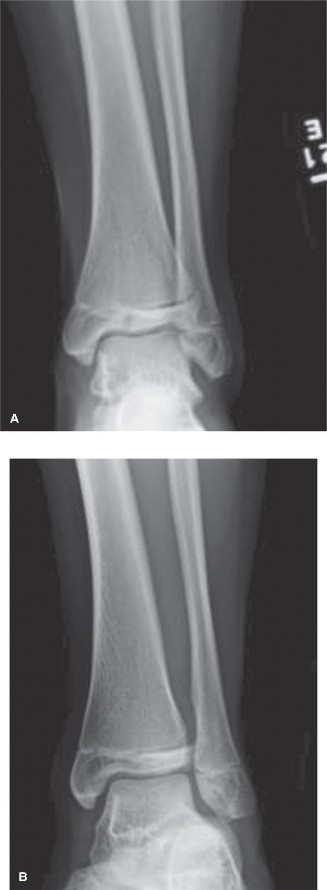

CASE 10 You are called to the emergency room to evaluate a 13-year-old male complaining of acute right ankle pain. He reports that he injured his ankle earlier in the day when another player “took him out” during a soccer match. He was unable to bear weight through the right lower extremity and was brought promptly to the hospital for evaluation and management of his injury. An anteroposterior radiograph of the patient’s ankle is shown in Figure 10–14.

Figure 10–14

The correct answer is (B). The radiograph shown demonstrates a Tillaux fracture, the eponym used to describe transitional ankle fractures in adolescents characterized by two main fragments: one fragment being the anterolateral distal tibial epiphysis and the second including the tibial metadiaphysis, the physis, and the posteromedial epiphysis. On an anteroposterior radiograph, the fracture line appears to run through the physis and exit through the epiphysis. The anatomic structure attached to this piece is the anterior inferior tibiofibular ligament (AITFL), one of the primary syndesmotic ligaments of the ankle. Chopart injuries involve the midtarsal joint. The Chaput fragment is another eponym (used more commonly in adult ankle fractures) to describe the fracture piece that remains attached to the AITFL. The anterior talofibular ligament (ATFL) is the most commonly injured structure in lateral ankle sprains.

This metaphyseal fragment is often called a “Thurston–Holland” fragment. Salter–Harris III injuries involve the physis and then the fracture exits into the epiphysis (towards the joint). The injury depicted in Figure 10–14 is a Salter–Harris III. Salter–Harris IV injuries involve the growth plate, with extension of the fracture into both the epiphysis and metaphysis. Salter–Harris V injuries are crush injuries through the growth plate that are often radiographically indistinguishable from Salter–Harris I injuries initially, but have higher rates of physeal arrest due to the increased force that produces this injury.